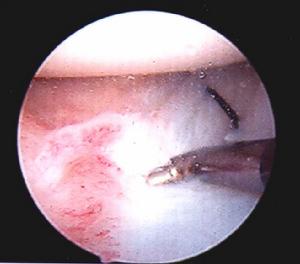

髖關節脫位--復位方法(1)後脫位的復位方法

④手術復位的適應症

手法不能復位,應考慮及時手術復位。髖臼上緣大塊骨折,須手術復位並作內固定。